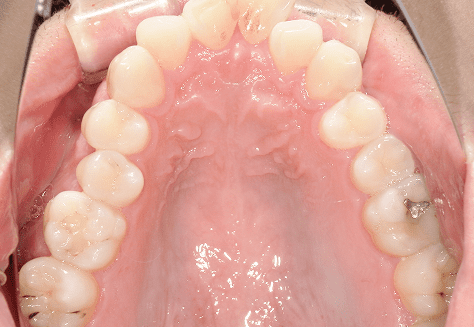

M.H

治療前

治療後

主訴

前歯が出ている。下の歯並びが特に気になる。奥歯でしっかり噛めない。

診断

上顎前突・叢生・シザーズバイト

年齢/性別

20代/男性

抜歯部位

下顎両側大三大臼歯(口腔外科にて)

上顎両側第一小臼歯・下顎左側側切歯

(当院にて5,500円×3) -

使用装置

上下エッジワイズ→インビザライン(PBM使用)

保定装置

上下ビベラリテーナー

診察料金

5,500円×44回

治療期間

3年6カ月